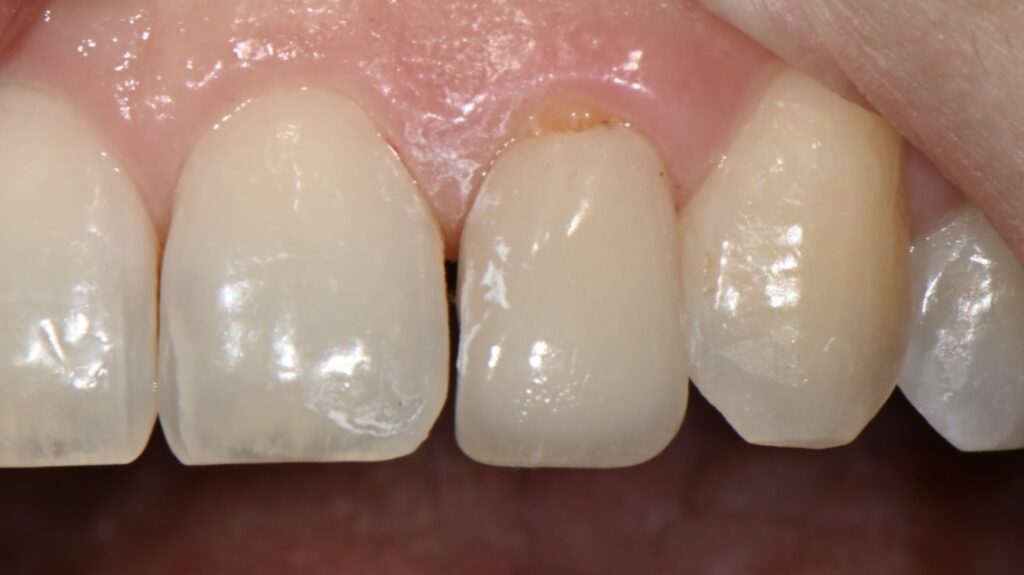

앞니 벌어진 부분과 왜소치 관련하여 문의주신 분입니다

나중에 왜소치 케이스에서설명을 드리겠지만

이 왜소치 케이스도 라미네이트가 불가능한 부분을

레진으로 극복한 케이스입니다

2주후 모습입니다

색상과 그리고 잇몸이 차오른걸 볼 수 있습니다